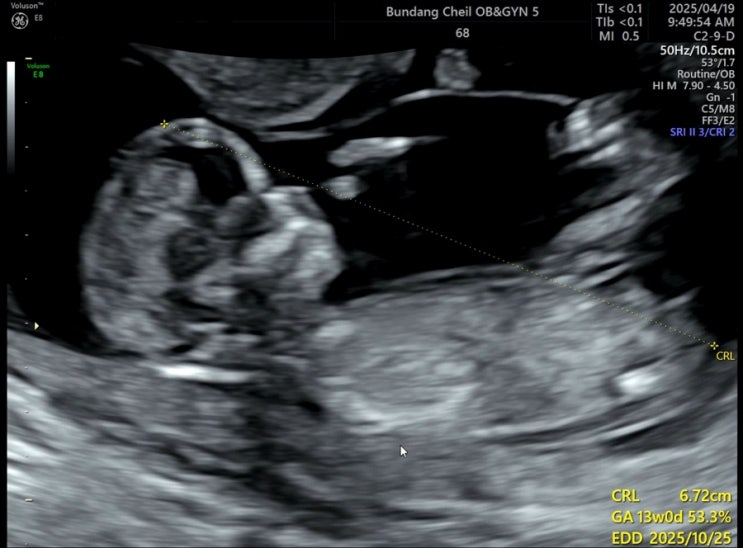

[13-17주]모자이시즘배아 양수검사 후기+비용

14주3일 샤워하고 머리감고나왔는데 아침부터 속이 울렁거리더니 결국 토하는데 암것도안나오고 힘들기만함...